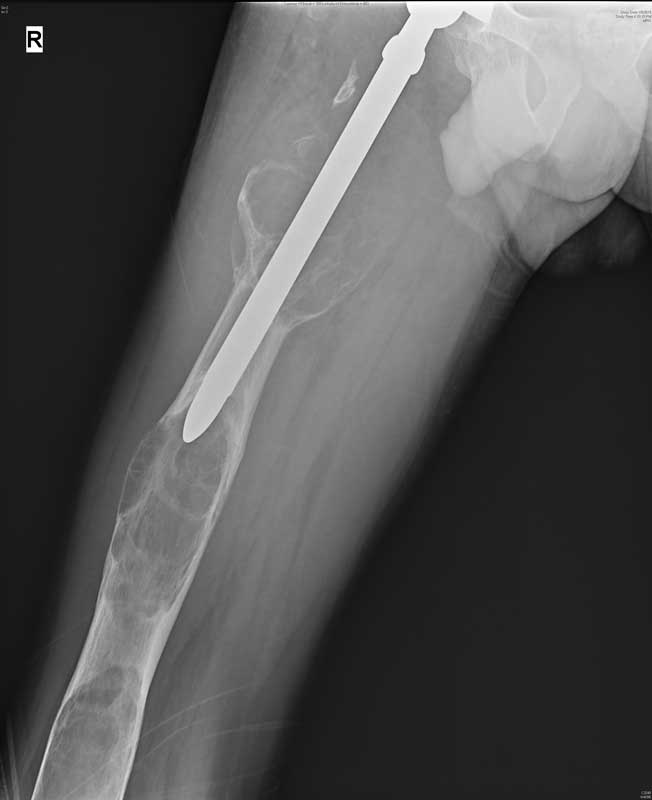

Sobidjon had tumor (bone malignancy) at multiple points on the bone between the knee and hip. He first underwent a total hip replacement in June 2011, which failed. The same was followed up by two more surgeries in his home country, which temporarily kept the cancer at bay but failed to have the desired result. Sobidjon Juraev found it difficult to walk and lead a normal life. The risk of recurrent cancer also posed a threat of permanent disability for the young man.

“We examined the patient thoroughly and discovered that the cancer in the Right femur bone had recurred. Now, it was at three points in the right femur bone between the hip and the knee, necessitating an amputation which would have been a life-long disability for a young man,” said Dr Rajeev K Sharma, Senior Consultant, Orthopedics & Joint Replacement Surgeon at Indraprastha Apollo Hospitals, New Delhi.

“Total Femoral Replacement in this case was a very difficult and rare surgery as it was a kind of a combination of hip replacement, knee replacement and thigh bone replacement. To be able to get rid of the cancer completely, we needed to remove the entire stretch of thigh bone from the right hip to the right knee and reconstruct the same artificially. It was a challenging surgery as it involved the removal of whole thigh bone at the same time. The challenges included threat of post-surgical infection, knee and hip instability and damage to the nerves and vessels of the area. However, in an 8-hour procedure we successfully removed the full cancerous thigh bone and replaced it with an artificial Total Femoral Implant,” added Dr Sharma.